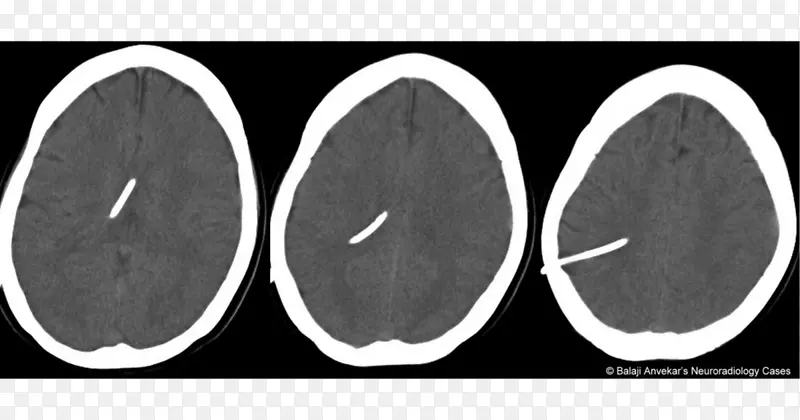

大脑白色字体-图片素材分享-空若网